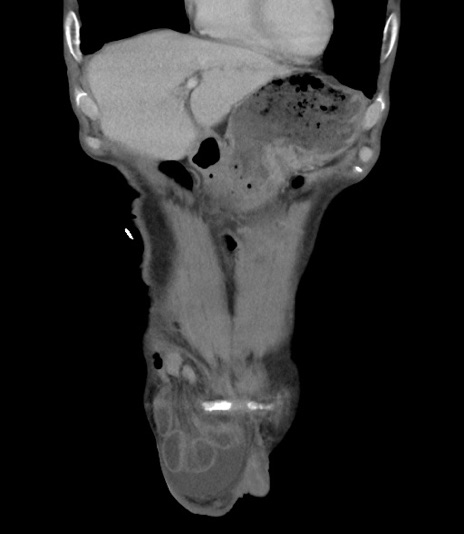

症例3(冠状断像)

【症例】 70歳代男性

【主訴】右鼠径部腫瘤、疼痛

【現病歴】本日朝より上記主訴あり、受診。

【既往歴】膀胱癌にて膀胱全摘、両側尿管皮膚瘻

【データ】WBC 5600、CRP 0.56